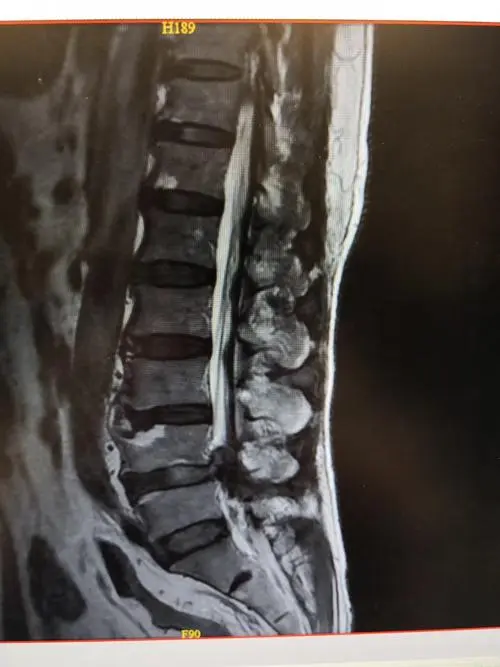

椎管狭窄症一般分为先天性(原发性)和后天性(继发性)。分为颈椎管狭窄、腰椎管狭窄和胸椎管狭窄。根据解剖部分,可分为中心狭窄、侧隐窝狭窄和神经根孔狭窄。

后天继发性椎管狭窄是由椎间盘突出、椎体增生、椎体滑脱、后纵韧带、黄韧带增生肥厚、钙化或骨化引起的,刺激脊髓、神经及周围血管炎症粘连,充血水肿"胀大",导致椎管狭窄。

椎管狭窄症的主要表现为明显的腰腿痛症状和间歇性跛行。椎管狭窄症患者步行100米或200米时经常会出现腰腿痛。弯腰休息一段时间或蹲下后,症状会立即减轻或消失。如果他们继续走,疼痛很快就会再次出现。脊柱后伸时症状会明显加重,前屈时症状会减轻。少数病例严重压迫马尾辫和神经根,甚至导致下肢不完全瘫痪。它给患者带来了巨大的疼痛。椎管狭窄症患者常说很多,但症状很少。检查脊柱偏差不明显,腰椎正常,但后伸时疼痛。直腿抬高试验正常或只有中度拉伸时疼痛。少数患者下肢肌肉萎缩,跟腱反射有时减弱或消失。